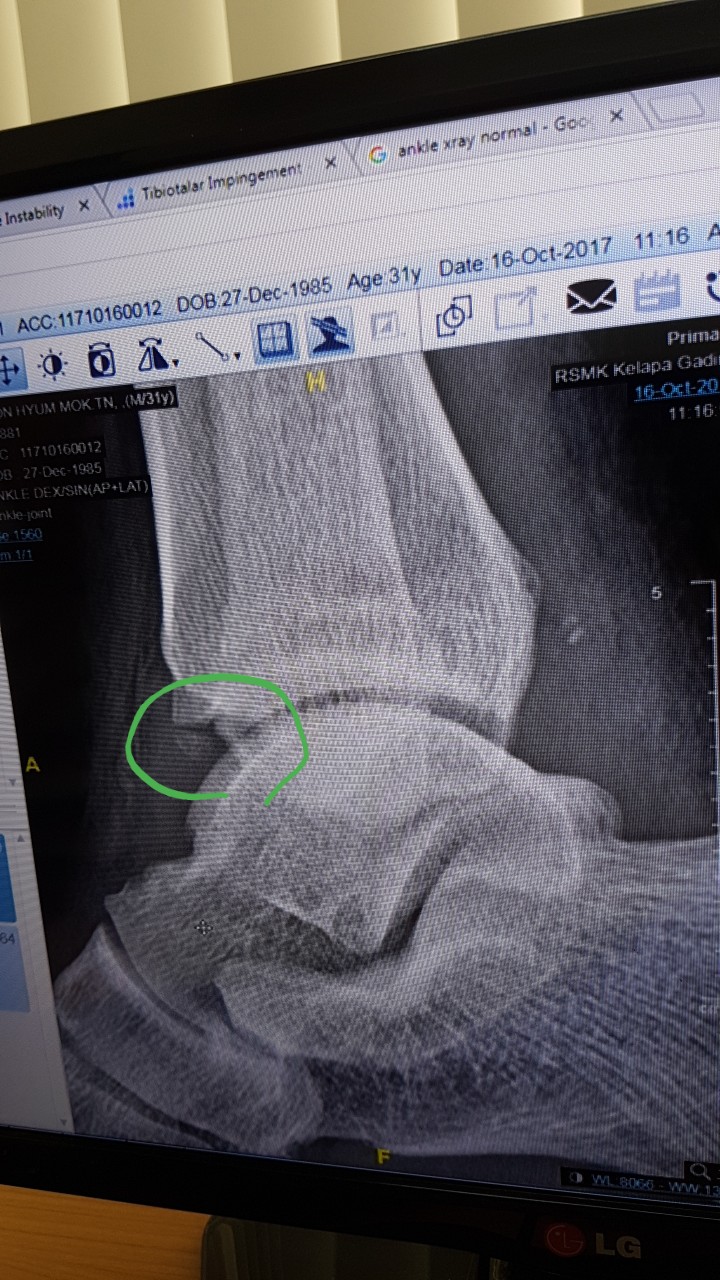

안녕하세요저는 인도네시아에서 현재 근무를 하고 있습니다.다름이아니라 2주전에 운전을 오래하고 골프를 치고 난 후 그다음부터 오른 발목이 시큰시큰 아프더니 결국 붓기가 올라 아직도 붓기가 빠지지 않고 있습니다.그리하여 한의원도 가보고 진통소염제 등 약도 먹어보다 어제 xray를 찍고 검사를 했는데 엑스레이 결과를 보고 Tibiotalar impingement 라고 합니다.수술을 해야한다는데 사실 외국이라 의학용어를 정확하게 몰라 다시한번 여쭙고자 합니다.필요시 한국에서 검사하고 수술할생각도 있어 한번 확인 부탁 드립니다아래의 사진에 동그라미 친부분을 제거해야한다는데 부탁드립니다어떤 수술을 해야하며 얼마나 걸릴까요 ? 제가 외국에서 근무를 해서 휴가기간을 정해야합니다.빠른답변 기다리겠습니다. ㅇ